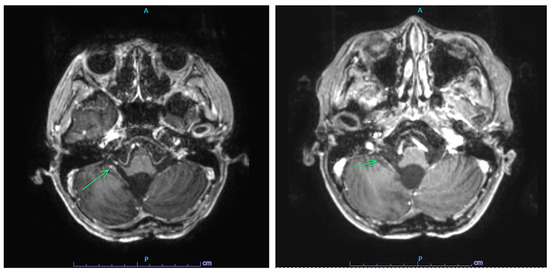

2.2. Case 2